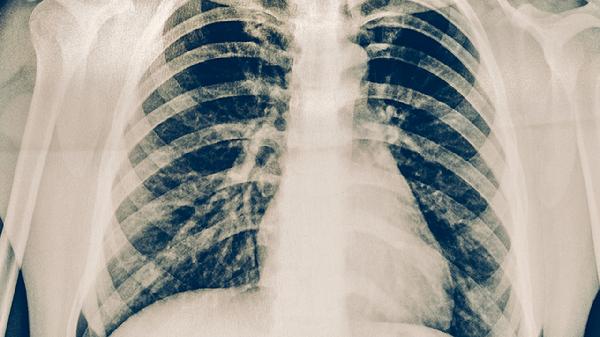

防治肺結(jié)核可以適量吃富含優(yōu)質(zhì)蛋白的食物如雞蛋、牛奶,以及富含維生素A的西藍(lán)花、富含維生素C的柑橘類水果、富含鋅的牡蠣等,同時(shí)需遵醫(yī)囑使用異煙肼片、利福平膠囊、吡嗪酰胺片、乙胺丁醇片、鏈霉素注射液等抗結(jié)核藥物。肺結(jié)核患者應(yīng)保證營養(yǎng)均衡,避免辛辣刺激食物,并嚴(yán)格遵循規(guī)范化療方案。

肺結(jié)核患者應(yīng)保持每日熱量攝入不低于2000千卡,采用高蛋白、高維生素、適量礦物質(zhì)的飲食結(jié)構(gòu)。烹飪方式以蒸煮燉為主,避免油炸燒烤。保證每日飲水1500-2000毫升促進(jìn)藥物代謝。居住環(huán)境需通風(fēng)良好,每日紫外線消毒,餐具單獨(dú)使用并煮沸消毒。嚴(yán)格完成6-9個月規(guī)范治療,不可自行停藥,定期復(fù)查胸部影像學(xué)和痰菌檢測。密切接觸者應(yīng)進(jìn)行結(jié)核菌素試驗(yàn)篩查。